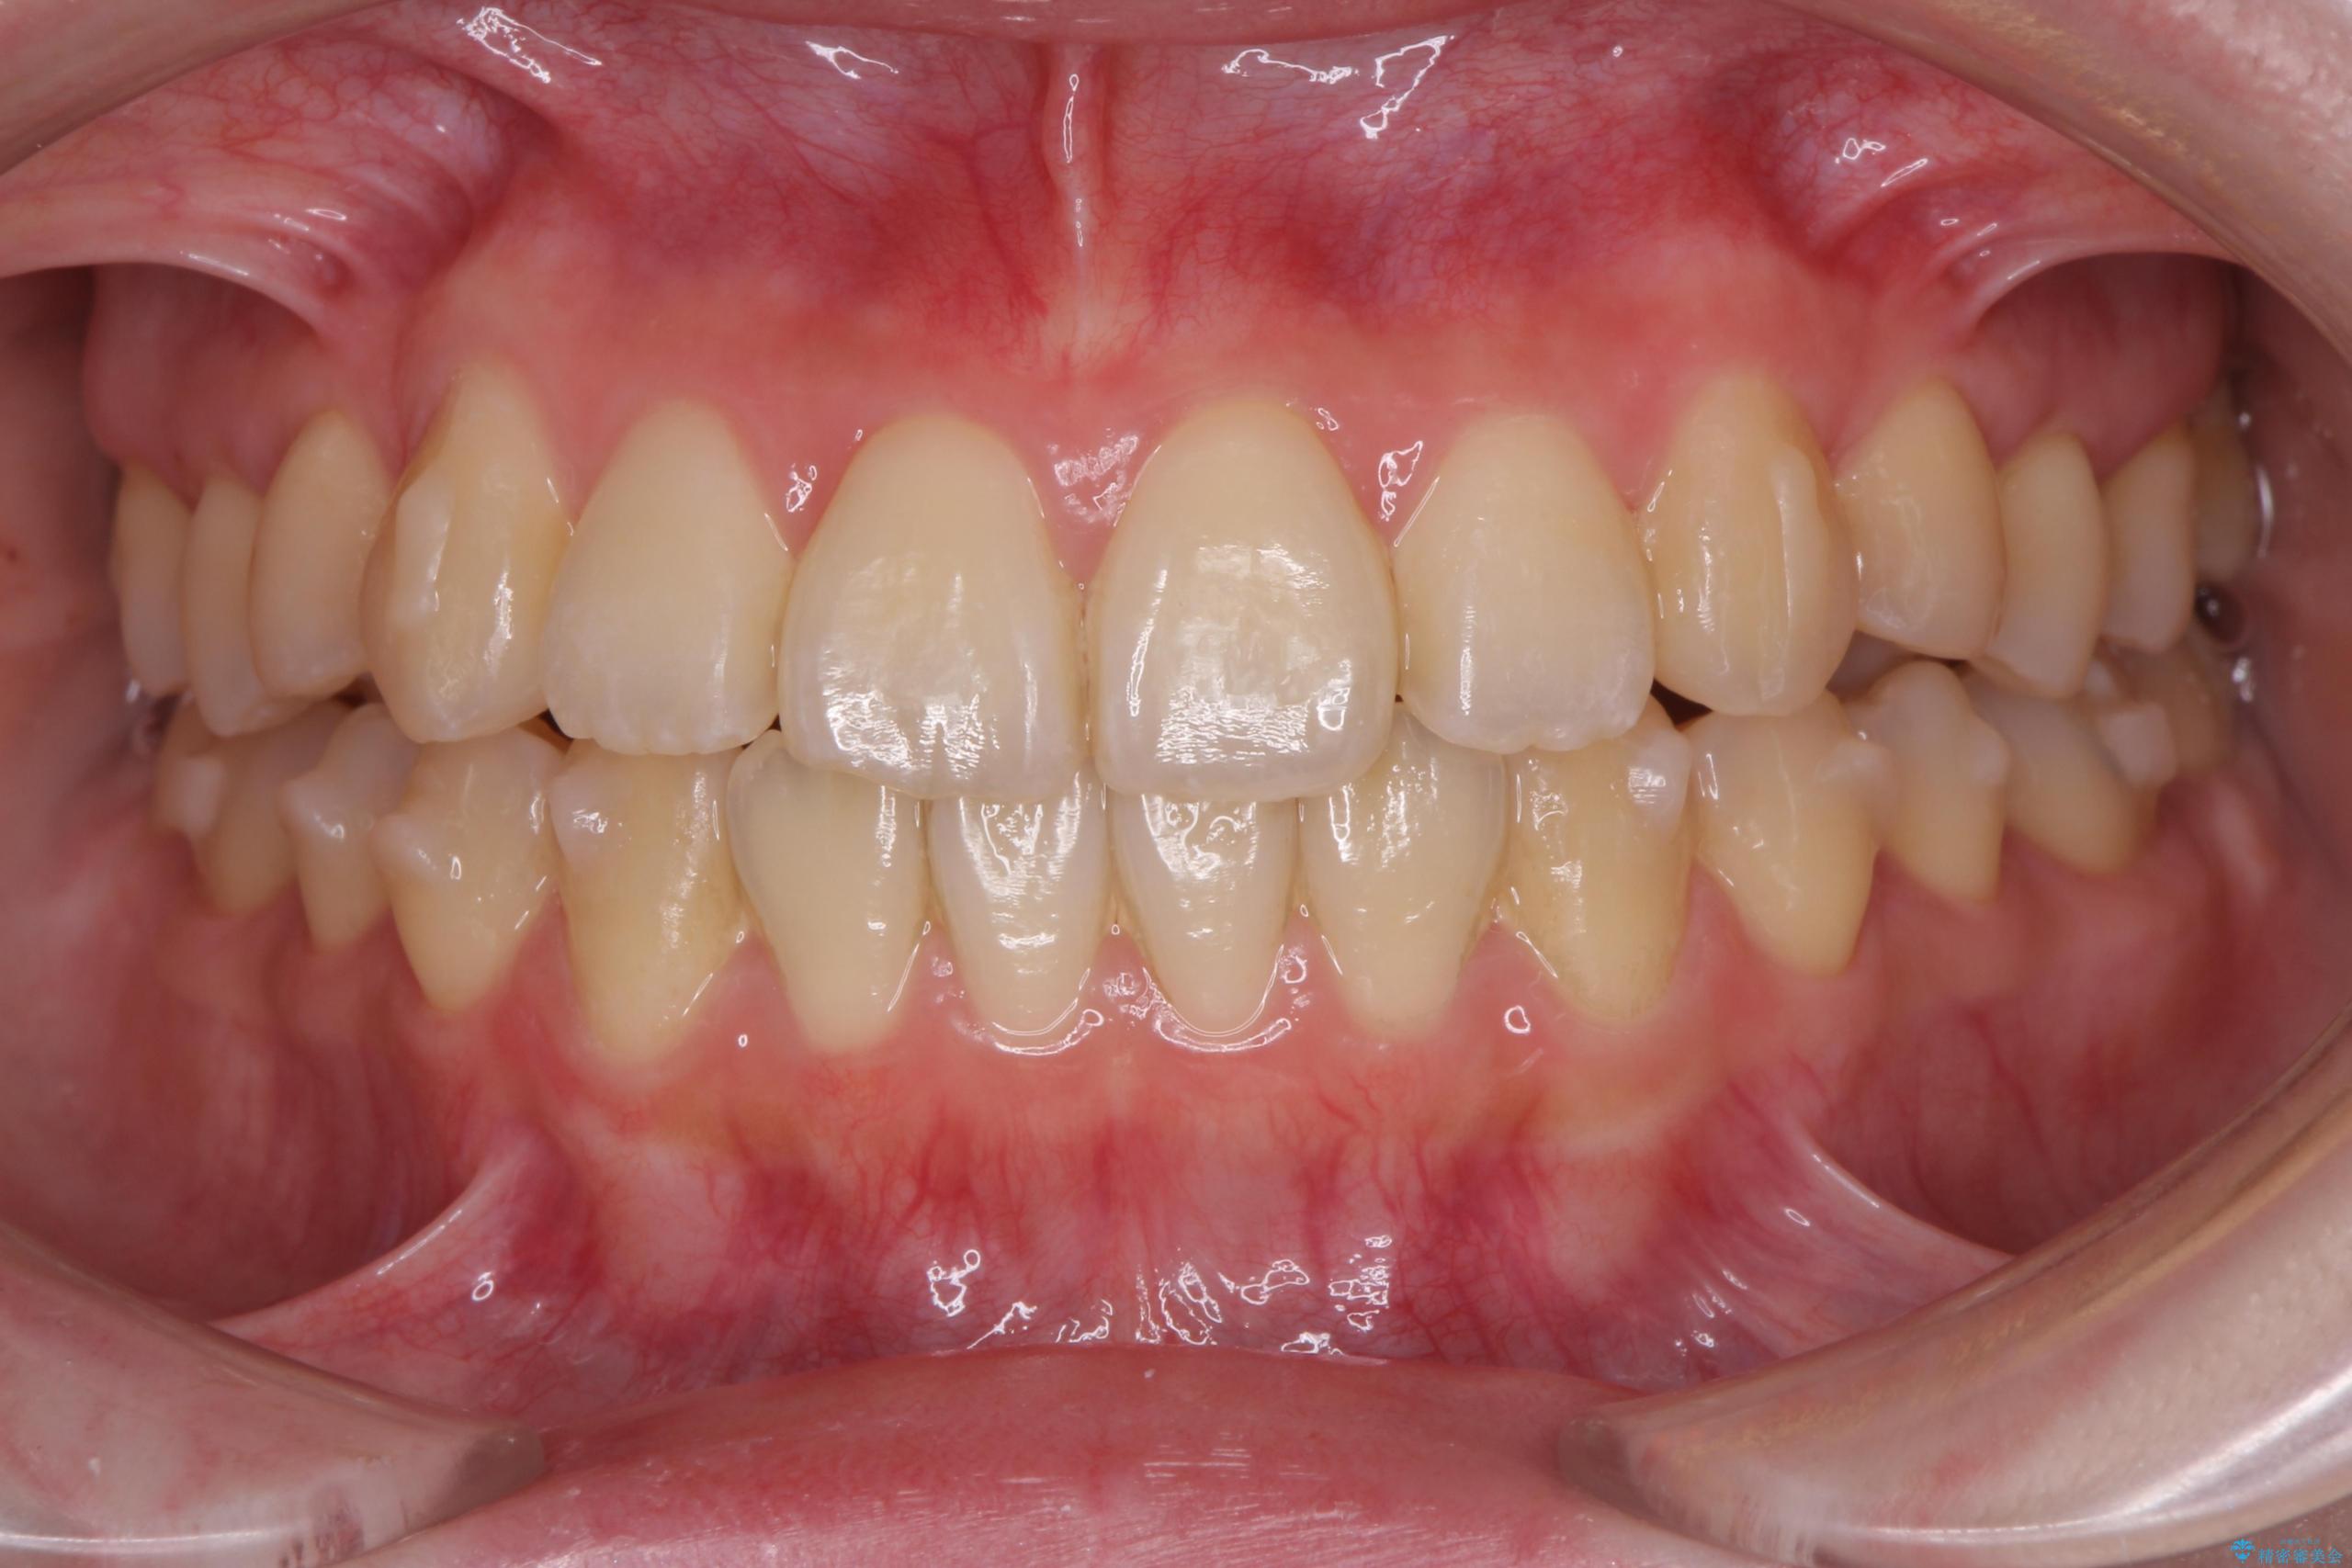

前歯のねじれが気になる、歯並びを改善したいとご来院された患者様です。

歯のねじれをきれいに取るのは、インビザライン(マウスピース矯正)だけでは難しい動きです。そのため、事前に4か月間の部分ワイヤー矯正を行い、治療期間を短くし、より美しい仕上がりを目指す計画です。

前歯が綺麗に並び、大変ご満足いただけました。